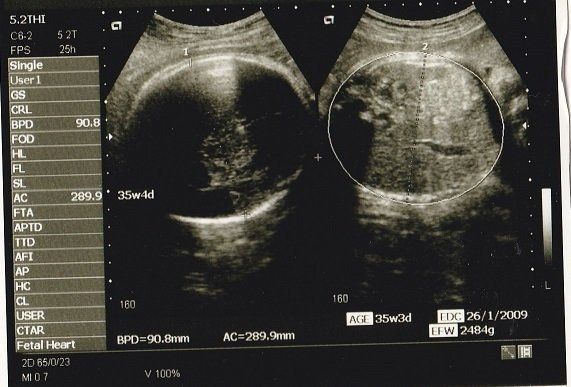

Tomomiさんの妊娠35週目のエコー写真 2週間で500gも成長!

推定体重が2620gになり、この2週間の急成長にびっくり。ついに帝王切開の手術予定日も決まり、出産に向けてもう一踏ん張り。入院の準備やご飯の作り置き、入院中の娘のお世話の仕方などをパパに指導し、ドキドキの2人目出産は目前に。